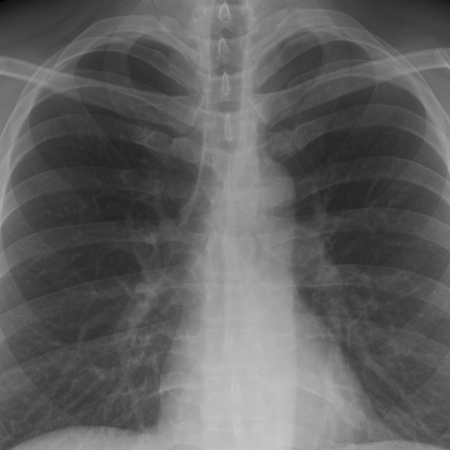

The AI platform identifies and analyzes suspicious findings in chest X-rays.